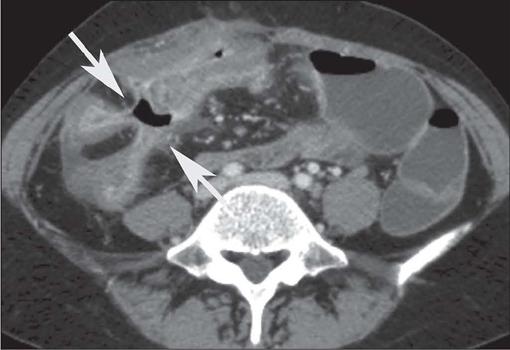

Crohn's disease is an inflammatory bowel disease that can affect any segment of the gastrointestinal tract. It has a variable clinical course, with alternating periods of disease activity and remission. Because the incidence and prevalence of Crohn's disease have been increasing, evaluation by imaging methods has become more important. The most widely used methods are computed tomography enterography, magnetic resonance enterography (as an elective examination), and contrast-enhanced computed tomography (in the context of emergency). Computed tomography enterography and magnetic resonance enterography are useful for diagnosis, follow-up, evaluation of complications, and prognosis. Both can be used in order to evaluate the small bowel loops and the associated mesenteric findings, as well as to evaluate other abdominal organs. They both also can detect signs of disease activity, fibrosis, penetrating disease, and complications. The interpretation of such changes is essential to the multidisciplinary approach, as is the standardization of the nomenclature employed in the reports. In this paper, we review and illustrate the imaging findings of Crohn's disease, using the standardized nomenclature proposed in the multidisciplinary consensus statement issued by the Society of Abdominal Radiology, the Society of Pediatric Radiology, and the American Gastroenterology Association, with recommendations for descriptions, interpretations, and impressions related to those findings.

克罗恩病是一种炎症性肠病,可累及胃肠道的任何节段。其临床病程多变,疾病活动期和缓解期交替出现。由于克罗恩病的发病率和患病率一直在上升,通过影像学方法进行评估变得更加重要。最常用的方法是计算机断层扫描小肠造影、磁共振小肠造影(作为选择性检查)和增强计算机断层扫描(在急诊情况下)。计算机断层扫描小肠造影和磁共振小肠造影对诊断、随访、并发症评估及预后判断均有帮助。两者均可用于评估小肠肠袢及相关肠系膜表现,以及评估其他腹部器官。它们还都能检测疾病活动、纤维化、穿透性病变及并发症的征象。对这些改变的解读对于多学科诊疗方法至关重要,报告中使用的命名标准化也同样重要。在本文中,我们使用腹部放射学会、儿科放射学会和美国胃肠病学会发布的多学科共识声明中提出的标准化命名,回顾并阐述克罗恩病的影像学表现,并对与这些表现相关的描述、解读及印象给出建议。